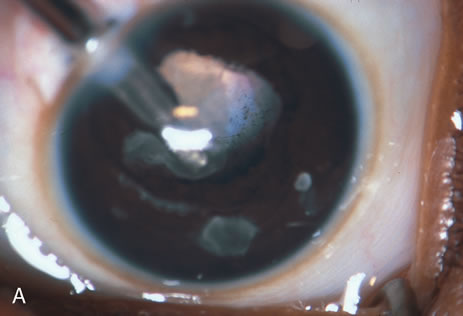

The most common application of the Nd:YAG laser in ophthalmology has been to open an opacified posterior lens capsule. The opacified capsule is commonly referred to as a secondary membrane (Fig. 6). A capsulotomy is recommended when there is a decrease in visual acuity that is due to opacification of the posterior lens capsule. This can cause either partial or complete obstruction of the visual axis. Judging the extent of a capsule's opacity and its effect on the patient's visual development may be difficult, especially in young or nonverbal children or in the presence of amblyopia. Signs that vision is decreased in a child are decreased light reflex on retinoscopy, presence of an ocular deviation, usually esotropia; decreased visual function; failure of the visual acuity to improve with occlusion; and a reduction in vision in spite of occlusion and accurate correction of the refractive error. During the evaluation, it is important to exclude other causes of these signs. Once it has been determined that the posterior capsule of the lens is causing the vision to be decreased (even slight opacity that decreases acuity to 20/30 or 20/40), photodisruption or opening of the posterior capsule is indicated.

Fig. 6. This child developed a secondary membrane after cataract surgery. The posterior capsule was not opened at the time of surgery.